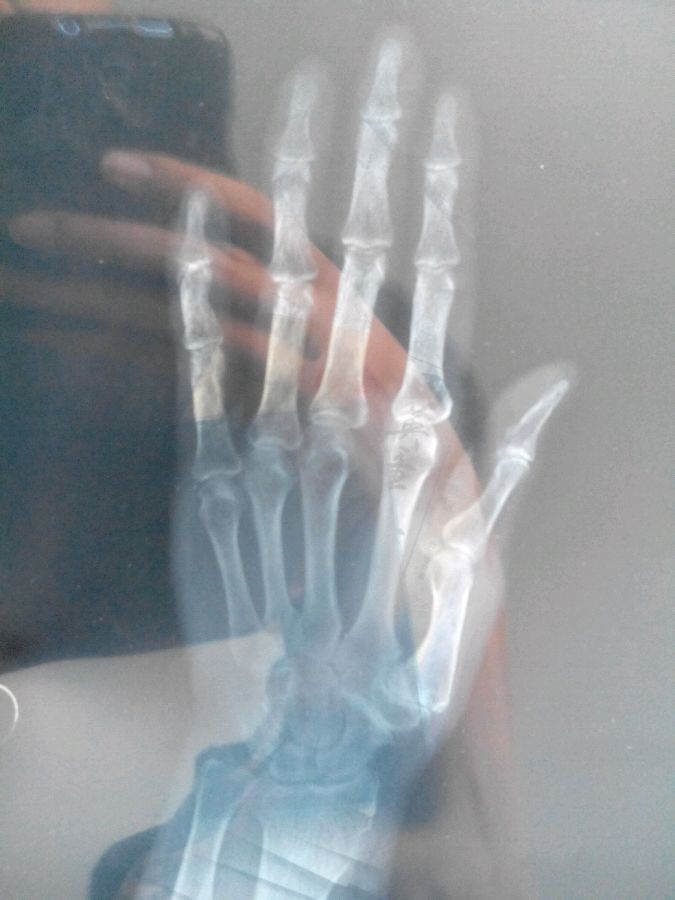

女 - 42岁、 完整 -